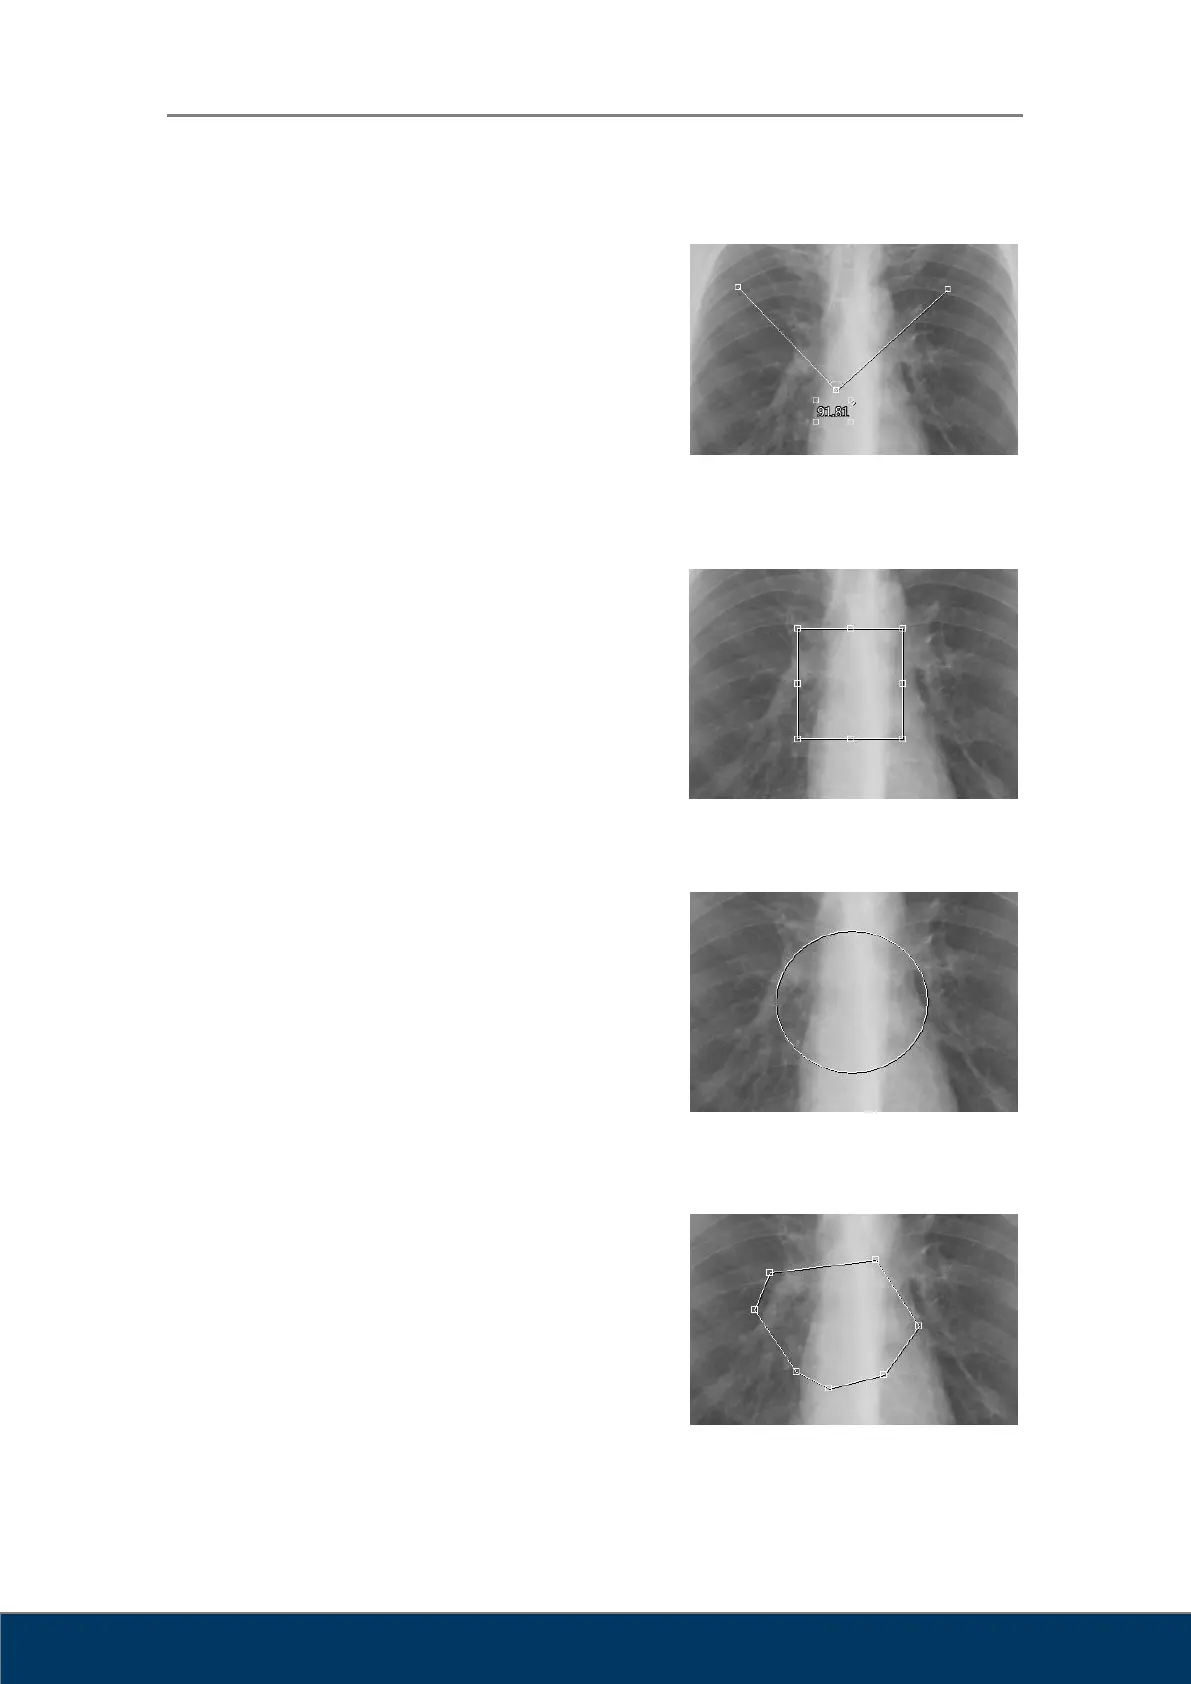

Ángulo: Mide el ángulo. Haga clic en el punto

central del ángulo que desee medir y, a

continuación, haga clic en los dos puntos de

control. Puede desplazar las dos neas a la vez

arrastrándolas. También puede desplazar

cualquiera de los dos puntos de control. También

puede cambiar la posición de los valores de

medición arrastrándolos con el ratón.

Rectángulo: Dibuja un rectángulo. Haga clic con

el ratón en la posición que desee de la esquina

superior izquierda del rectángulo y, a continuación,

arrastre el cursor hasta la posición deseada de la

esquina inferior derecha del rectángulo y suelte el

botón del ratón. Haga clic en la zona interior del

rectángulo para desplazarlo. Arrastre los puntos

de control para cambiar el tamo del rectángulo.

Elipse: Dibuja una elipse. Haga clic con el ratón

en la posición en la que desee que el punto

superior y el punto del extremo izquierdo de la

elipse se crucen, arrastre el cursor hacia abajo a

la derecha y suelte el botón del ratón cuando

haya conseguido el tamaño y la forma deseados.

Haga clic en la zona interior de la elipse para

desplazarla. Arrastre los puntos de control para cambiar el tamaño de la elipse.

Dibuja un polígono. Cada vez que haga clic, se

adirá un punto de control. Haga doble clic

cuando haya terminado de dibujar el polígono.

Haga clic en la zona interior del polígono para

desplazarlo. Arrastre los puntos de control para

cambiar las esquinas del polígono.